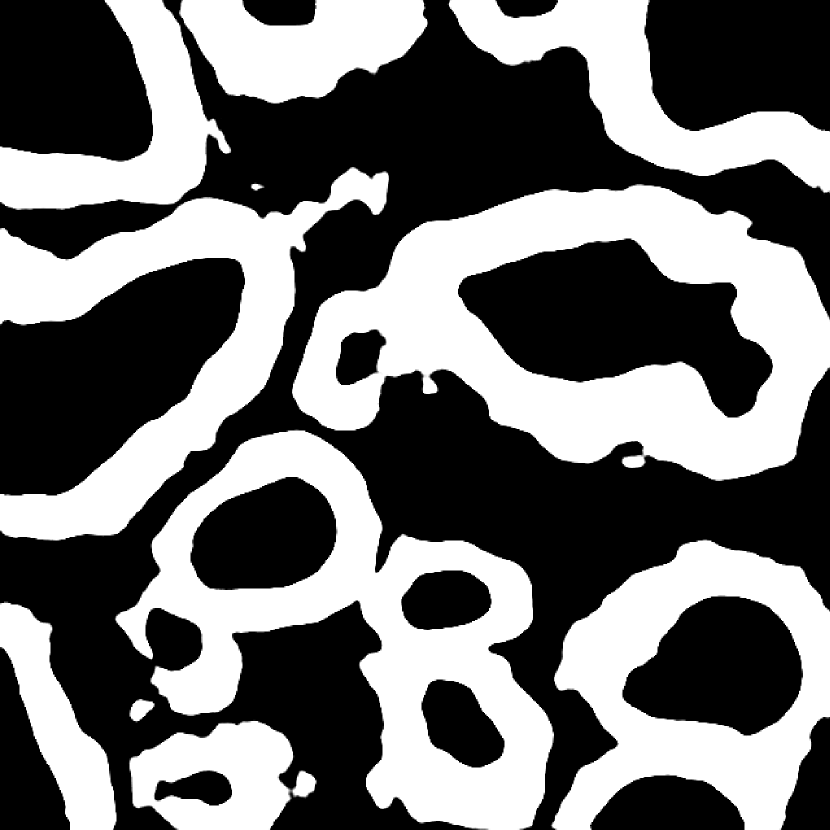

Fig. 3 shows two image examples, their ground-truth masks, and the final segmentations generated by competing models. Comparing with U-Net, Res-Seg based models generally have fewer false positives. Comparing with Res-Seg-Net, Res-Seg-Net and Res-Seg-Net both generate cleaner outputs, which can serve as an evidence that hierarchical refinings are effective in improving segmentations in both accuracy and robustness. These effects can be clearly seen within the areas highlighted with green boxes.

We fed Res-Seg-Net with the patch in the first row of Fig. 3, and output their segmentations maps of each layer in Fig. 4. The segmentation refining process is evident, as more and more details are added to the finer outputs. The low resolution segmentations tend to catch the primary shapes of the target objects. Moving upwards, they not only provide guidance for fine-resolution labelings to capture more details, but also set up certain guard to reduce the appearance of noisy spots.